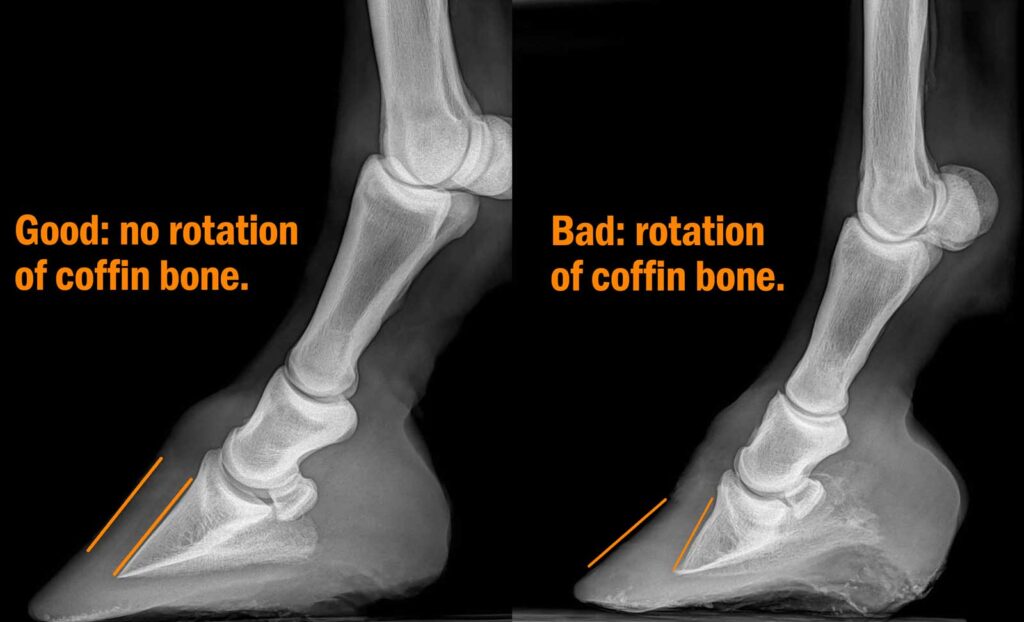

Founder (aka laminitis) in horses is a very serious condition of the foot caused by the coffin bone rotating and pointing towards the horse’s sole. This is extremely painful and in some instances it may be necessary to euthanize the horse.

- Movement or rotation of coffin bone

Be prepared to tell your veterinarian your horse’s medical history along with their vaccination history. This will give your vet a head start prior to a comprehensive physical and lameness examination which includes palpation of certain areas for pain, heat, and inflammation. A static flexion will also be done to check out the range of motion. The veterinarian will ask you to trot your horse off to observe the horse in motion. A hoof tester is used next to put pressure on certain areas of the foot to find the exact location. In addition, the veterinarian will need to get x-rays of the hoof to check the alignment of the coffin bone and may also do an ultrasound as well for a more detailed view.